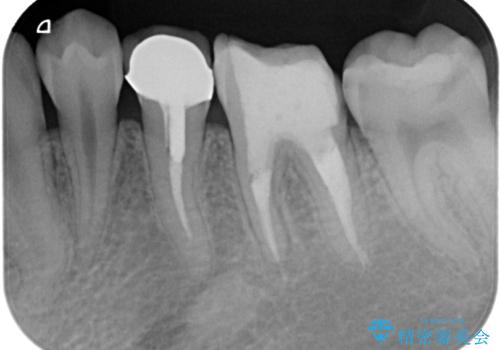

右下奥歯は既に根管治療が行われており、セラミッククラウンが装着されていました。

セラミッククラウンを壊して再度根管治療を行い、その後セラミッククラウンを装着する方法か、外科的に歯根の先端を切除し、炎症の原因である細菌を取り除き治癒を図る方法とを提案し、極力クラウンを壊さずに治療を進めたいとの希望により、歯根端切除術を行うこととしました。

治療から9か月ほどが経過した時点で、違和感や痛みはなく、歯根端切除術を行った右下は、レントゲンでも良好な経過が確認できました。